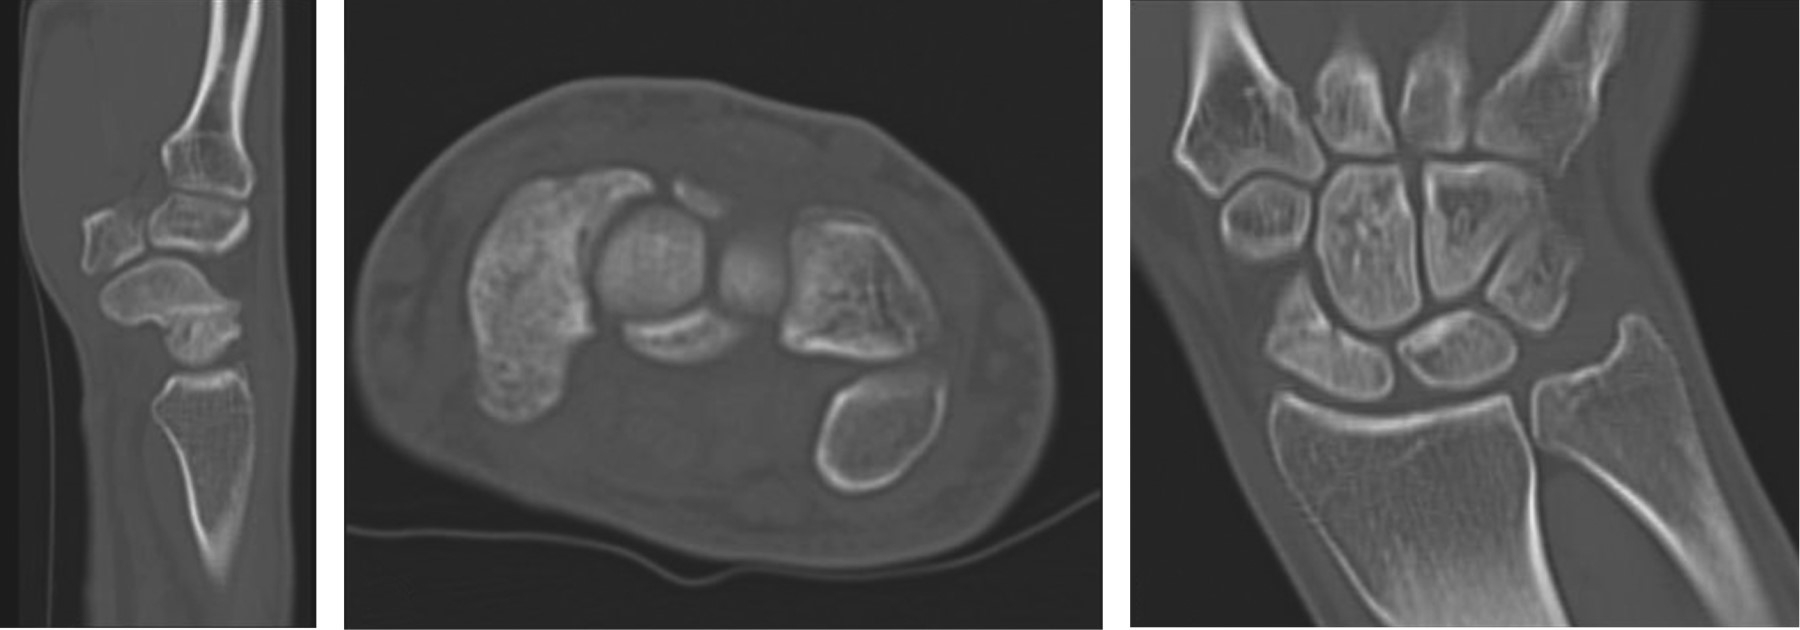

A 28-year-old right-handed male, with no comorbidities, sustained a wrist injury when he fell from his own height and landed with an outstretched right hand. He evolved with swelling, limitation of movement, and tenderness on palpation in his anatomical snuff box. He was initially assessed in another institution where through plain radiographs the diagnosis of scaphoid fracture was made. It was classified as a Herbert and Fischer type B2 (complete displaced scaphoid waist fracture) (Figure 1). Consequently, he was immobilized with a below-elbow cast without the inclusion of the proximal phalanx of the thumb. After three weeks, the patient removed his cast and decided to abandon the treatment and medical follow-up. At seven months he consulted again for pain. Once more, posteroanterior, lateral, and scaphoid (30° wrist extension, 20° ulnar deviation) plain radiographs of the wrist were requested (Figure 2). The fracture exhibited absence of consolidation. Due to the evolution time (more than six months from the initial trauma), a scaphoid nonunion was diagnosed. A CT scan was requested to assess displacement. This revealed a Herbert type D nonunion (established nonunion), with no density alteration in the scaphoid fragments and no displacement (Figure 3). According to the Slade and Geissler classification, it was a grade II nonunion, with no sclerosis, no bone cysts, and a small resorption edge. Surgical treatment was indicated, but the patient refused. Then he returned to our institution 10 months after the initial injury. He presented with pain in the anatomical snuffbox, on axial compression of the first metacarpal, and on palpation of the scaphoid tubercle. Mobility was similar to the contralateral side but painful (visual analogue scale [VAS] 7/10) (Table 1). Surgical treatment was once more indicated. The patient was then lost in follow-up and returned to control 15 months after the initial injury without having undergone any type of treatment or immobilization. He showed a spontaneous clinical improvement, a complete absence of pain (VAS 0/10) and range of motion, and grip strength similar to the healthy contralateral side (Table 1). Plain radiographs and CT scan with 3D reconstruction were requested. The new images showed scaphoid consolidation (Figures 4 and 5).

Figure 3